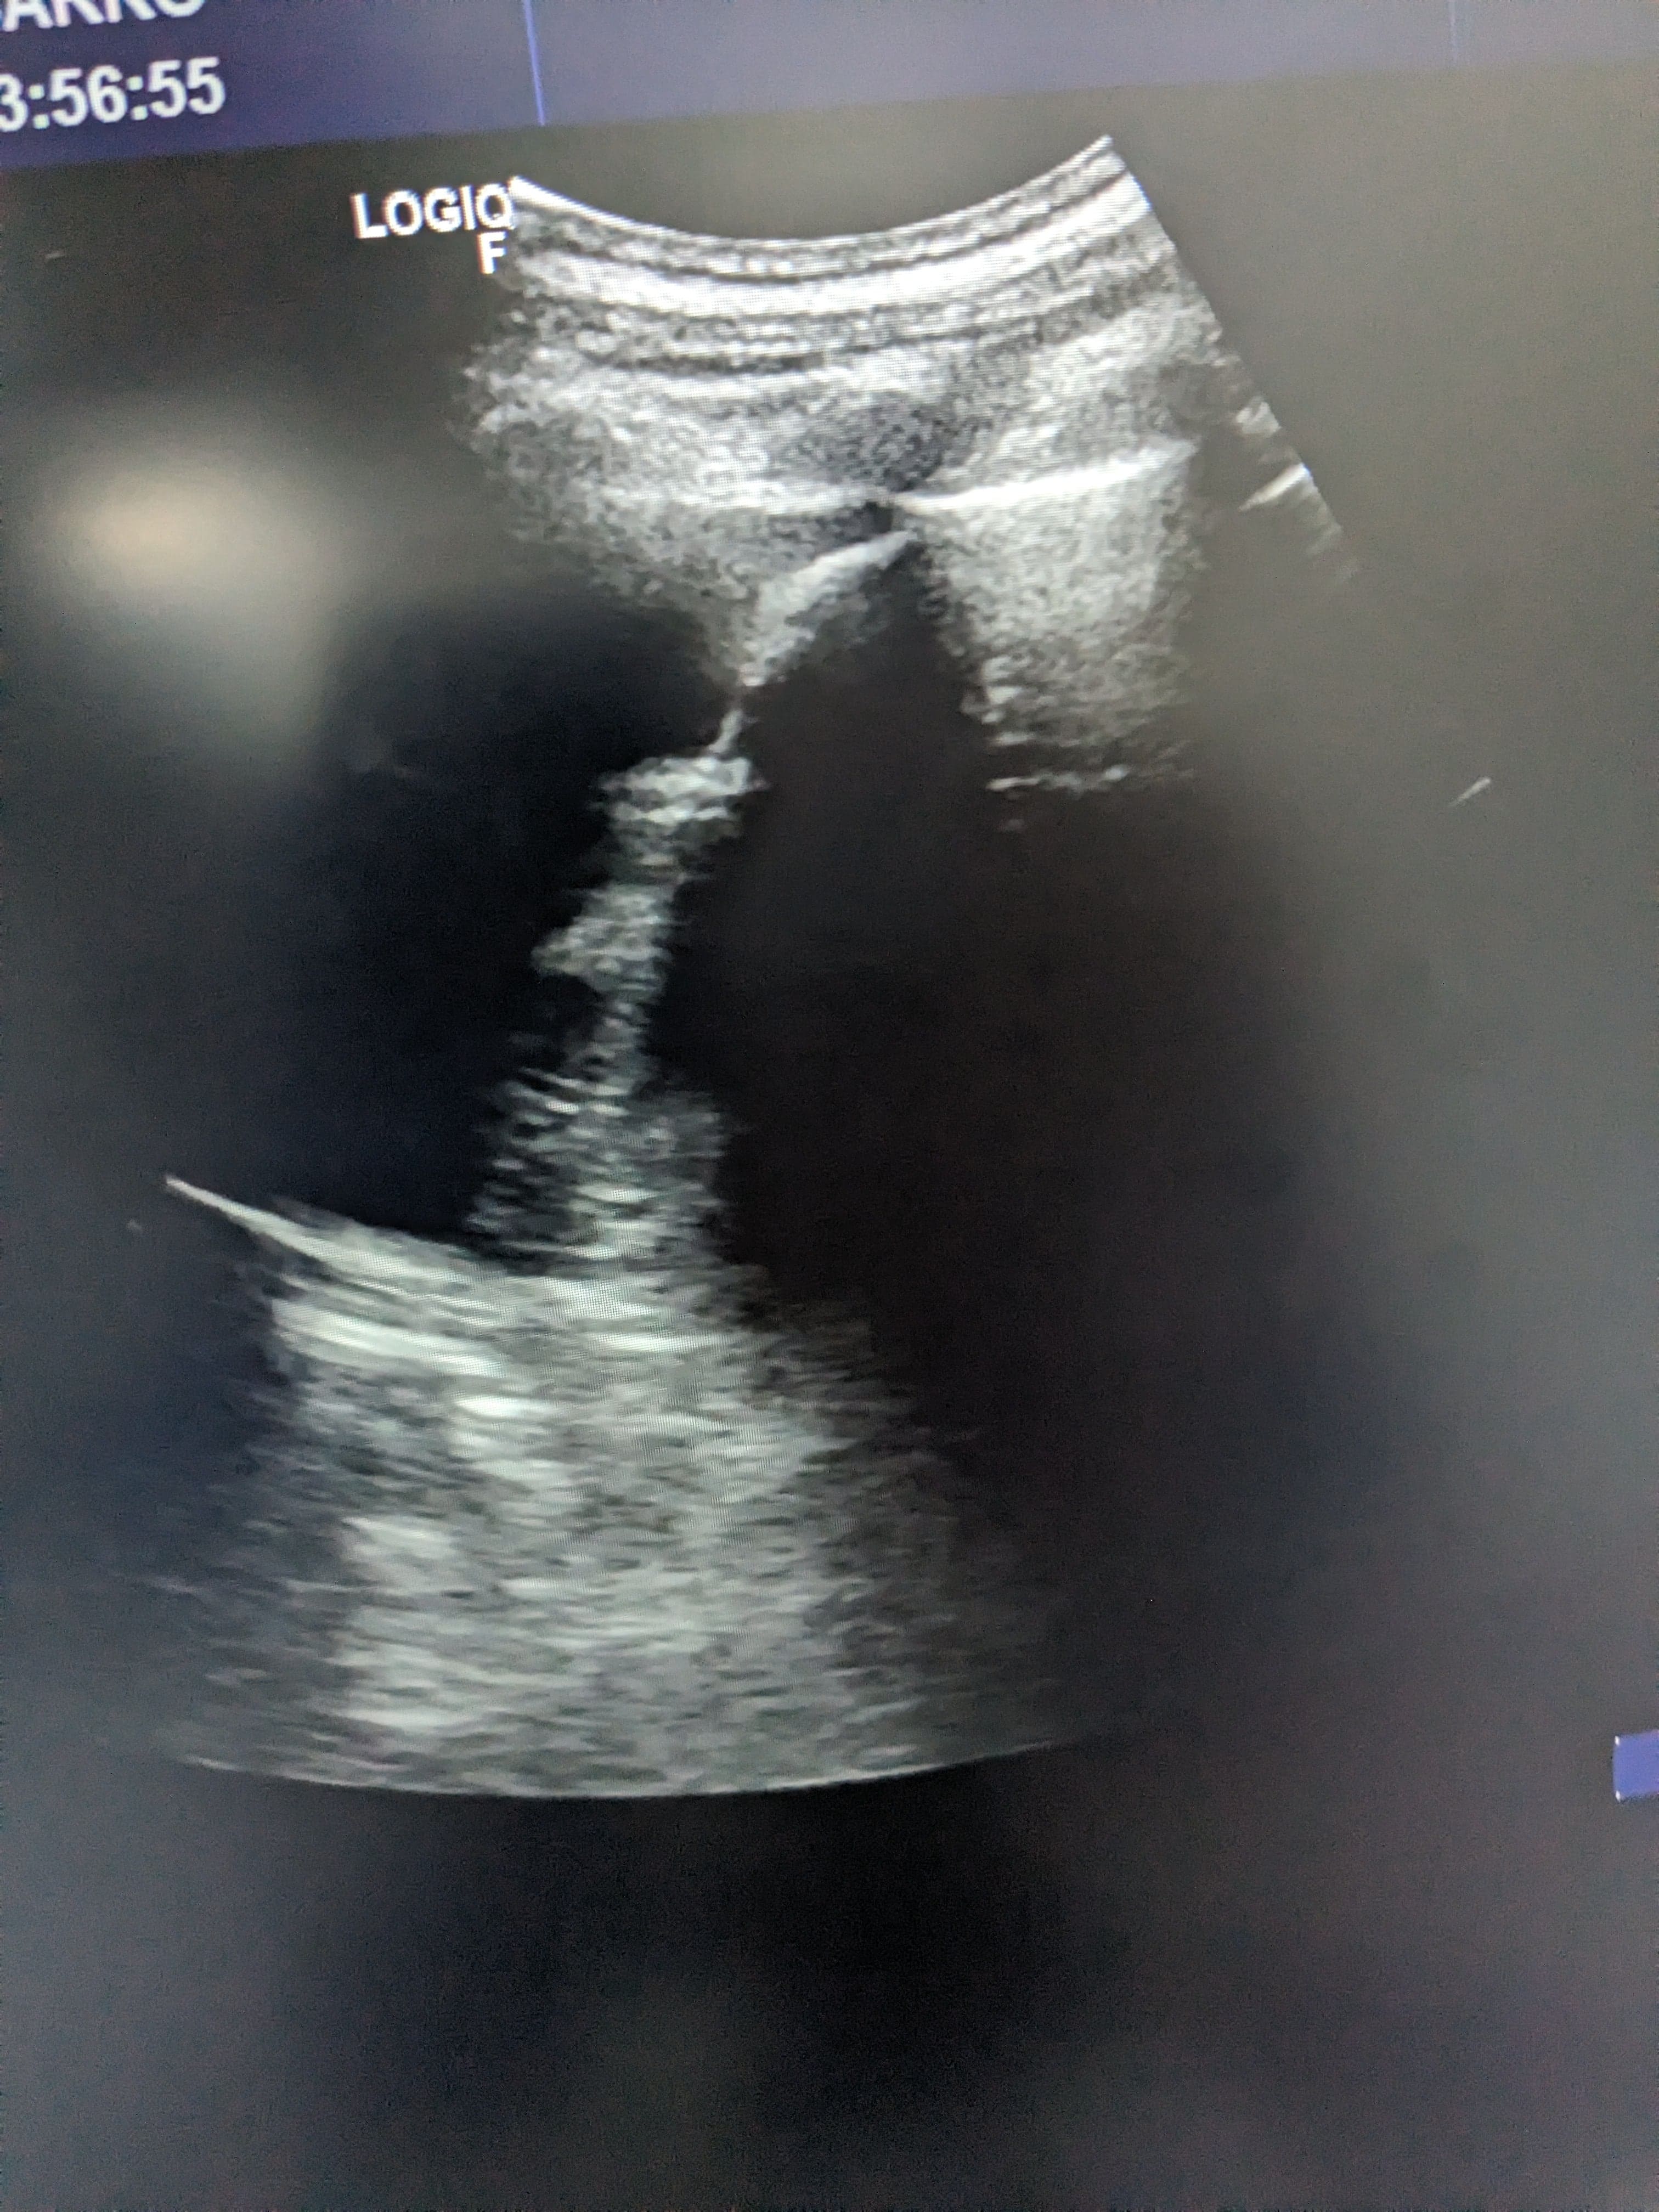

Se hace ecografía clinica en la consulta de atención primaria, observamos derrame pleural en pulmón izquierdo hasta medio campo pulmonar.

Se orienta como derrame pleural de origen desconocido por lo que se deriva a urgnecias del hospital de referencia para valoración de pruebas complementarias y tratamiento.

Rx torax: derrame pleural izquierdo. Sin pinzamiento de seno derecho. Sin infiltrados ni condensaciones.